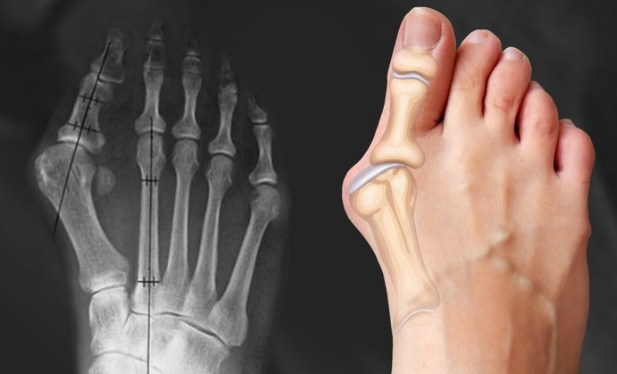

Новый онлайн-курс по массажу при проблемах связанных с искривлением большого пальца стопы, образованием "шишки", "косточки" на ноге, плоскостопии и сопутствующих патологиях

Положительный и достаточно быстрый эффект от процедуры, достигается благодаря грамотному последовательному подходу, который основан на биомеханических взаимосвязях, рефлекторных реакциях и коррекции скелета стопы. При проведении такого массажа, в организме массируемого происходит множество положительных биохимических процессов и ответных реакций как на клеточном, так и на тканевом уровнях. В частности, улучшается микроциркуляция и питание тканей стопы и голени, улучшается проводимость сосудов, как следствие устраняются застойные явления и отечность ног, восстанавливается эластичность связок и сухожилий. В совокупности это положительно влияет на здоровье ног. Уходит болезненность в области переднего отдела стопы, в частности в зоне вальгусного искривления и образования типичного выступа, известного как «шишка» или «косточка» на большом пальце стопы. Шаг становится более мягким, лёгким, непринуждённым, естественным.

Урок №4. Система большого пальца стопы. Вальгусная деформация, механизм развития патологии, биомеханика

Урок №5. Методика и техника массажа при вальгусной деформации большого пальца стопы. Протокол работы